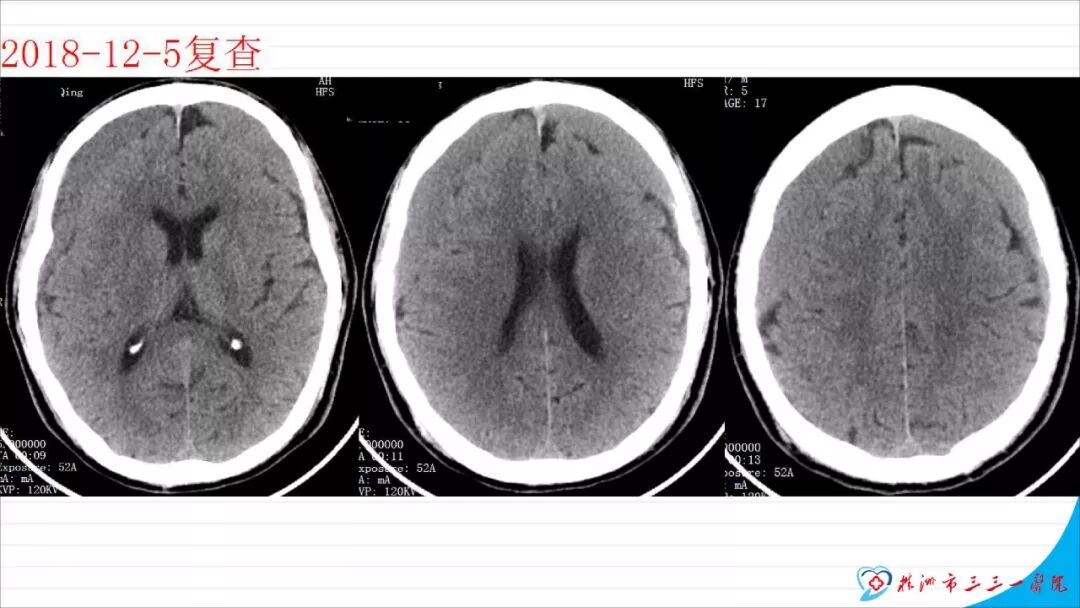

本文以“慢性硬膜下血肿自然演变一例”为题,恰当!因为此例患者系从急性硬膜下血肿自然演变而来。只是长期口服他汀没有起到预防作用。本例患者与其说是阿托伐他汀治疗慢性硬膜下血肿无效,还不如说是阿托伐他汀不能阻止急性硬膜下血肿向慢性硬膜下血肿演变的过程,当然,后续急性血肿变成慢性后,阿托伐他汀似乎也没有发挥治疗作用。需要指出的是,单药阿托伐他汀治疗急性硬膜下血肿并无成功病例报道,但是,本例报道还告诉我们,它还不能阻止急性硬膜下血肿向慢性血肿演变,值得关注。 谈到阿托伐他汀治疗慢性硬膜下血肿,我们是始创者。为此,看到作者似乎有点抱怨的情绪,我得做些解释。我们ATOCH试验,验证的是阿托伐他汀治疗慢性硬膜下血肿比安慰剂能更有效促进血肿吸收,没有发现也没有努力去验证阿托伐他汀治疗慢性硬膜下血肿100%有效,因此发生治疗无效很正常。 保守治疗的始作俑者是英国人,他们1962年就提出地塞米松治疗慢性硬膜下血肿。但是,迄今为止,无论是英国人提出的地塞米松、美国人提出的氨甲环酸或血管紧张素转换酶抑制剂,还是德国人提出的塞來西布,日本人提出的汉药,国内许多单位自行研究提出的血府逐瘀丸,作者单位的“传统”方法红花注射液治疗慢性硬膜下血肿都没有经历严格随机双盲安慰剂对照研究,也从未被大宗病例报道证实过有效。由于未被RCT(随机对照临床试验)证实过,加上一部分慢性硬膜下血肿不必治疗也可以自我吸收(这在我们ATOCH里的安慰剂组中已经观察到,但我们发表论著时没有刻意提出这一点而已),除他汀疗法之外的药物疗法被怀疑是否真具有疗效就顺理成章了。这也是我们的阿托伐他汀治疗慢性硬膜下血肿在保守治疗药物队伍中“一骑绝尘”的理由。后续西南医科大学和香港中文大学还均报道使用阿托伐他汀可以预防慢性硬膜下血肿术后复发。而且,除了有RCT结果支撑其有效性外,安全性明显优于上述各个西药又不像中药或汉药那么含糊,也使得阿托伐他汀成为目前保守治疗慢性硬膜下血肿应用最多的药物。 但毫无疑问,实践中确实屡屡有发现效果不佳的病例。为什么会这样呢?可能有2个理由: 1、确实存在一部分对他汀治疗反应不佳的患者。我们的ATOCH中,阿托伐他汀试验组就有11例患者因无效转去接受手术(对照组则多达23例); 2、ATOCH试验长达8周,有些患者家属和医生都没有耐心等待8周。也就是说,没有等到药物作用显现就转保守治疗为手术治疗。在同样状况下,即使作为发明者,我也不敢“阻扰”患者转手术治疗,因为这意味着风险转嫁。而这种“保守治疗未到时间”(这样提可能不严谨,因为没有规定时间,只有经验时间)就转手术治疗,会增加阿托伐他汀治疗慢性硬膜下血肿的“无效率”。 有鉴于此,我们团队在张建宁教授指导下,从2014年就开始优化阿托伐他汀疗法,本人以此优化的独门方法就治愈了多达200余例各种慢性硬膜下血肿患者。最近,有上海同行私下告诉我,他用类似我的优化方法保守治疗慢性硬膜下血肿多例,还没有失败过。我跟他开玩笑:“那是你治疗的病例还不够多。”实际这不是开玩笑,因为本人有失败经验。目前,我们团队正积极推进ATOCHII试验,就是要证明我们的优化疗法更加有效,期待奉献给世界一个更加好用的治疗慢性硬膜下血肿新方法。 最后需要特别指出的是,慢性硬膜下血肿与急性硬膜下血肿和亚急性硬膜下血肿并非一定有如父如子的“传承”关系。实践中,绝大多数患者都没有急性硬膜下血肿过程,尤其是老年患者第一次查影像学多数就可以确诊慢性硬膜下血肿了,患者之前并没有经历急性硬膜下血肿这种剧烈损伤过程。还有,脑转移癌可以发生类似慢性硬膜下血肿的血肿性病变,先天性蛛网膜囊肿、脑池囊肿术后常见并发症就包括硬膜下血肿。笔者诊疗慢性硬膜下血肿接近300多例,还见过教科书和个案报道没有记载的各种非脑外伤相关慢性硬膜下血肿的病例。相比于脑外伤引起的急性和亚急性硬膜下血肿,慢性硬膜下血肿是处理简单且病情稍显轻微的疾病,但其发生机制却远比急性和亚急性硬膜下血肿更为复杂,值得进一步深入研究。 江荣才 教授 副主任兼NICU主任 天津医科大学总医院神经外科![]()